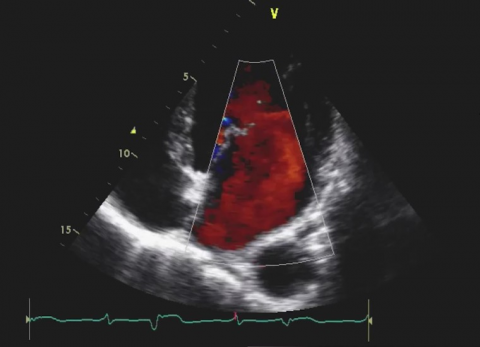

Wideo Echokardiografia. Przypadek 31

dr hab. n. med. prof. UJ Andrzej GackowskiPacjent z narastająca dusznością z podejrzeniem niedomykalności aortalnej.